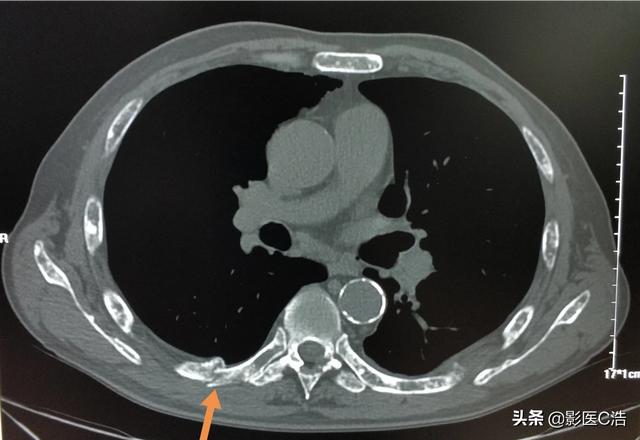

数日前、肺がんの骨転移の患者を診断したばかりで、彼の症状は長期的な腰背部痛で、彼らはいつも腰椎の筋肉の緊張、または腰椎椎間板ヘルニアに苦しんでいると思ったが、気にしなかった、本当に痛みが深刻で、下肢の神経症状が現れ、唯一の検査のために病院へ、そのCT検査に与えられた、明らかな椎骨破壊があることがわかった。......病歴を詳しく調べると、患者は長期的に咳の症状があるため、肺がんの骨転移が強く疑われ、肺のCT検査を行ったところ、主な焦点は......巨大な肺がんであることがわかった。

46歳の男性が、腰の持続的な痛みのために受診した症例があった。腰痛は椎間板ヘルニアと考えられた。レントゲンを撮ったが異常は見られなかった。わずかな骨破壊を起こす骨転移はレントゲンでは見えないし、椎間板ヘルニアもレントゲンでは見えない。だから、転移の可能性については特に考えなかった。1週間後、それでも改善が見られないのでCTを撮りに来たところ、腰椎が食べられていた。 このような画像を見て、画像診断医は転移の可能性を考えるに違いないと思い、胸部CT検査をするよう患者に勧めたところ、案の定、肺に腫瘤があり、肺がんの骨転移と考えられ、後日病理検査で確認された。